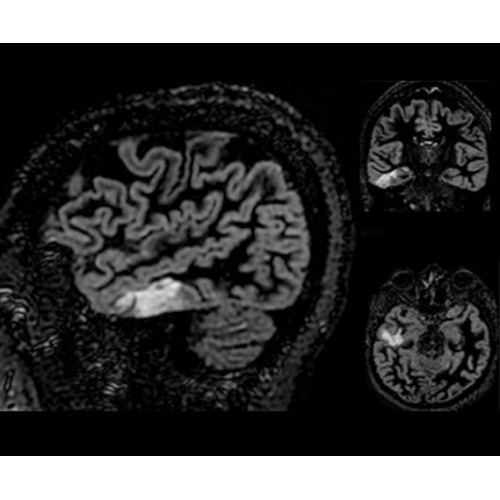

SIGNA PET/MR 3.0T — это гибридная система, в которой совмещаются две принципиально разные технологии — магнитно-резонансную томографию (МРТ) и позитронно-эмиссионную томографию (ПЭТ). Система отличающийся высокой чувствительностью и эффективностью и предназначена для диагностики в области онкологии, неврологии, кардио-васкулярных исследований, исследований воспалительных процессов.

Компания GE Healthcare представляет революционную, полностью интегрированную систему SIGNA PET/MR1, в которой сочетаются времяпролетная технология (TOF) и возможности напряженности магнитного поля 3.0 Тл. Мы поможем вам поднять исследования на более высокий уровень. SIGNA PET/MR позволяет достичь впечатляющей точности и скорости исследований, а благодаря новейшей технологии реконструкции Q.Clear2 качество изображений улучшается в два раза. Кроме того, в систему включен полный набор клинических приложений и гибких катушек для проведения любых видов исследования, открывая для вас возможности визуализации, о которых вы даже не догадывались.

Кроме того, в результате использования технологии TOF и инновационной технологии реконструкции Q.Clear вы сможете добиться прекрасного соотношения сигнал/шум. А благодаря технологии нулевого времени эхо (ZTE) визуализировать костную структуру без ионизирующего излучения. Все эти разработки для улучшения качества сканирования и точности анализа помогут вам использовать весь потенциал ПЭТ/МРТ.

• МРТ с функцией нулевого времени эхо (ZTE) отличается точностью, возможностью персональных настроек и отсутствием ионизирующего излучения. Она приходит на смену традиционному исследованию на основе рентгеновского излучения. МРТ с функцией нулевого времени эхо (ZTE) на базе SIGNA ПЭТ/МРТ является более надежной и быстрой по сравнению с системами, использующими сверхмалое время эхо (UTE).